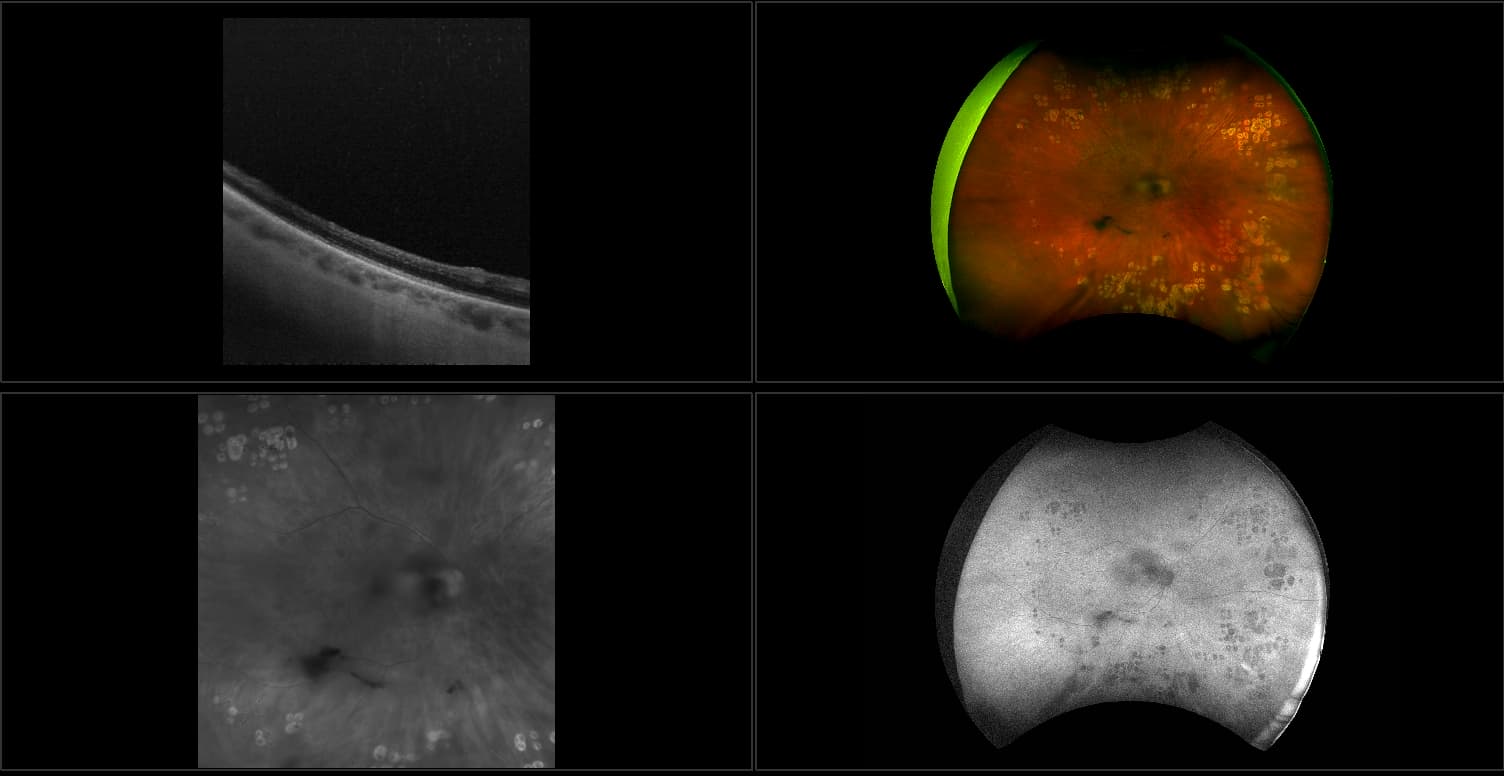

Acute multifocal placoid pigment epitheliopathy (AMPPE)

AMPPE affects otherwise young healthy adults and presents as a disorder affecting the retina, Retinal Pigment Epithelium and choroid. APMPPE is an acquired, self-limiting, inflammatory disorder.